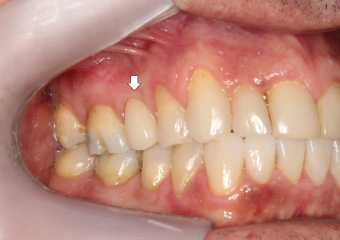

Elemento 15 fraturado